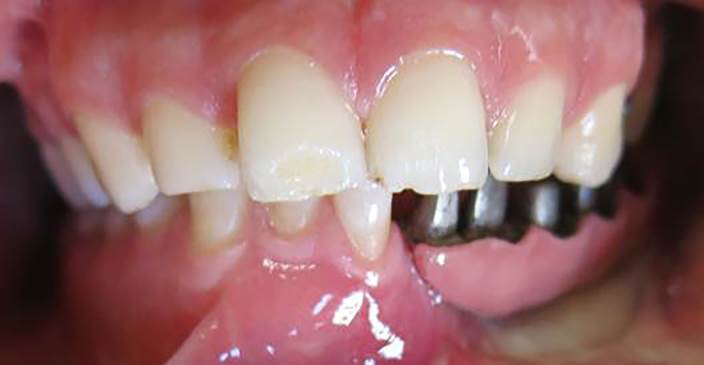

A 30-year-old partially edentulous patient was referred to the Implant Department of Tehran University, School of Dentistry, for prosthetic reconstruction (Figure 1, a and b). The patient had lost 6 teeth due to the trauma of a gunshot. Since the accident had occurred several years prevoiusly and the patient had undergone cosmetic plastic surgery, only a skin scar remained in his lower face. Three implants (Implantium, Dentium, Seoul, South Korea) were placed on the left side of the mandible (Figure 2, a and b). Regarding the increased interocclusal space and improper implant alignment, it was decided to use hybrid screw-retained and cement-retained implant (Toronto) prosthesis.

a) Occlusal view of the mandible after gunshot injury. b) Side view of the left side of the mandible after gunshot injury